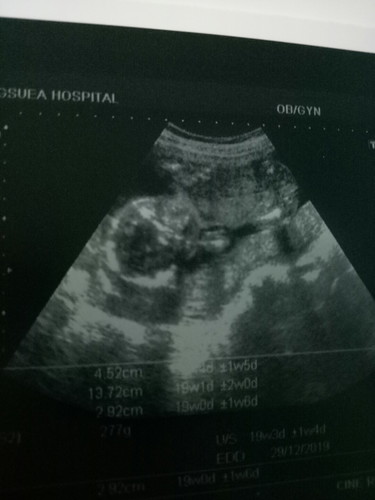

แม่ๆท่านใหนพอดูเป็นบ้างค่ะว่าชายหรือหญิงตอนนี้ท้องได้5เดือนแล้วค่ะ

เห็นแต่ตัวน้องค่ะ